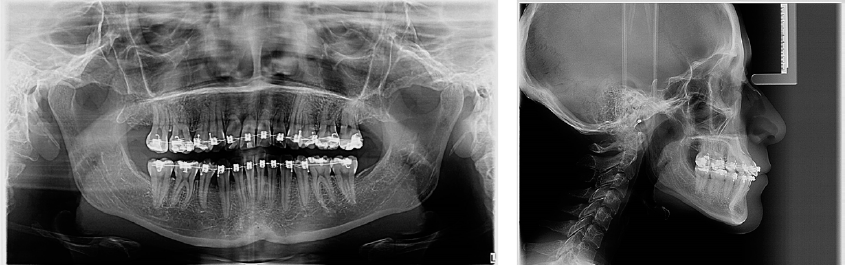

En el análisis facial se determinó una paciente dolicofacial con el tercio inferior aumentado, exposición disminuida de los dientes anteriores superiores al sonreír y perfil recto (Figura 1). A la exploración clínica se identificó dentición permanente con ausencia de los dientes 34 y 44, periodonto reducido estable, mucosa bien irrigada, frenillos bien implantados, líneas medias no concordantes, apiñamiento superior severo e inferior moderado; dientes 13 y 23 en supraoclusión Clase III molar, y mordida cruzada unilateral (Figura 2). Se solicitaron auxiliares diagnósticos incluyendo ortopantomografía y radiografía lateral de cráneo (Figura 3).

Figura 3 Estudios iniciales de ortodoncia, de izquierda a derecha, ortopantomografía y lateral de cráneo.

En la ortopantomografía se observaron 30 dientes; 28 erupcionados, terceros molares inferiores impactados, se confirmó la ausencia de los dientes 34 y 44, restauraciones extensas en 15 y 25. La paciente presentaba dilaceración y longitud radicular disminuida en los dientes 12 y 22. La relación corona-raíz en centrales superiores era 1:1 y existía una pérdida del reborde óseo en la zona de anteriores superiores e inferiores. El análisis cefalométrico reveló una Clase I esquelética con exceso vertical del maxilar y crecimiento horizontal (Tabla 1).